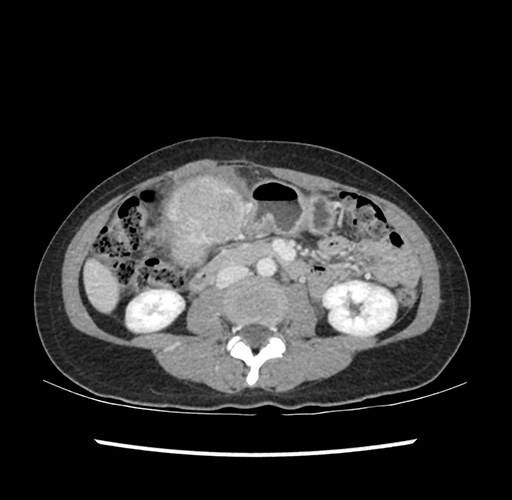

Imaging Analysis

Look through the patient's CT scan to identify any areas of concern for the necessary procedure.

Based on your CT findings, which issue(s) would give reason for "planned slowing down moment(s)" in this case?